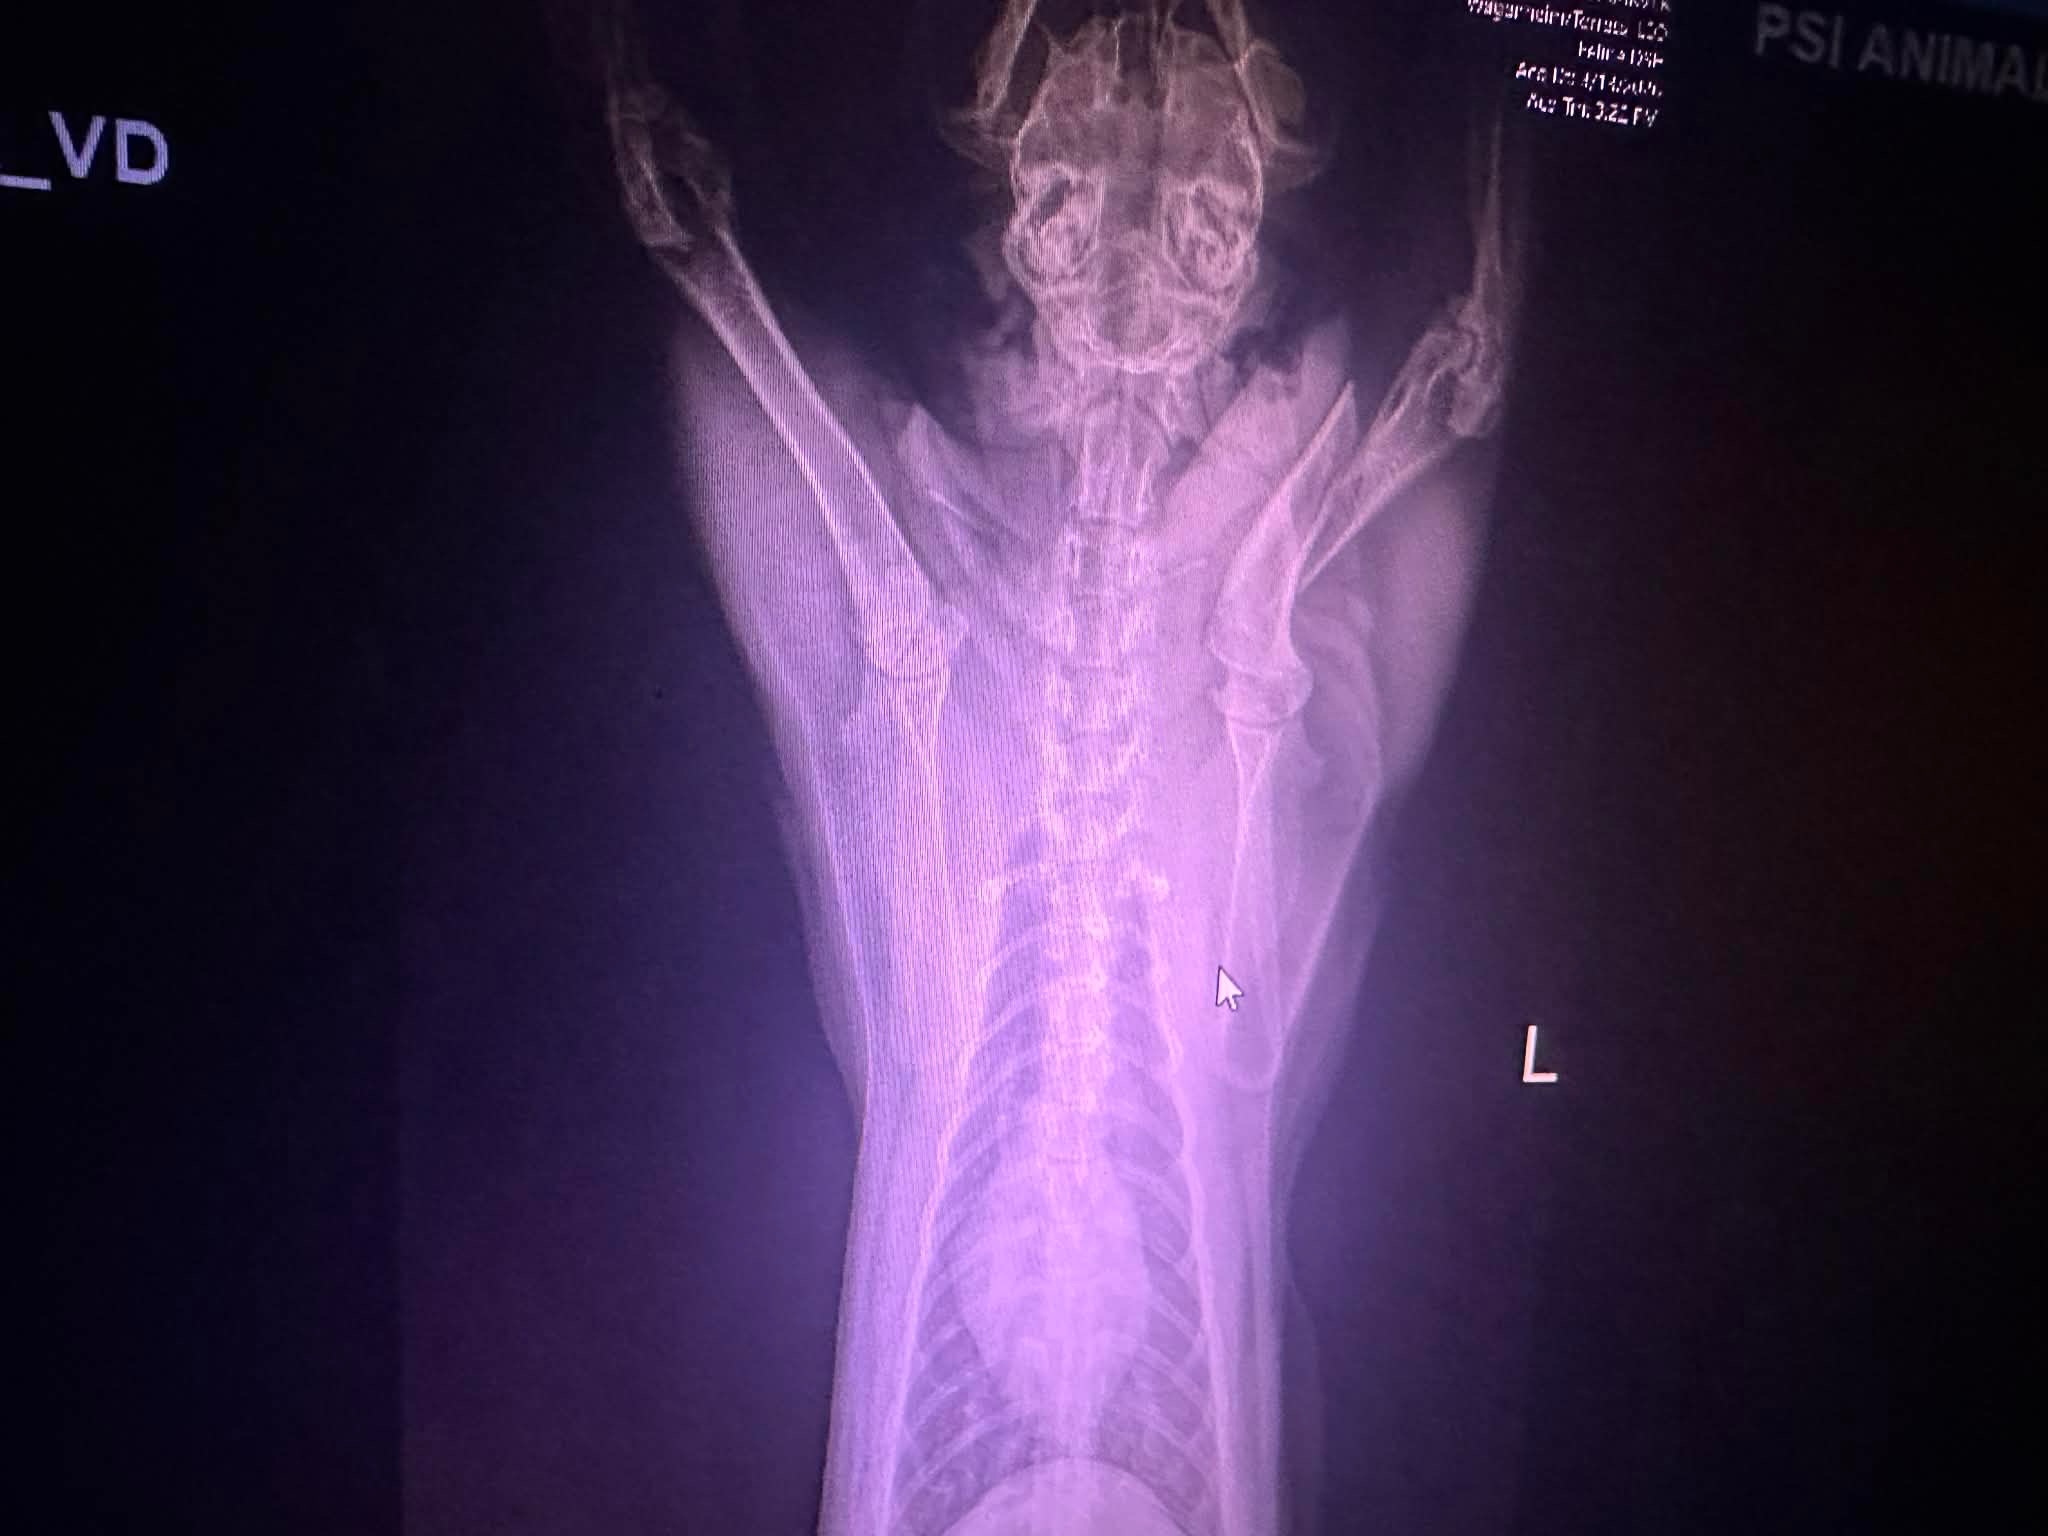

After sedation, X-rays, and a radiology consultation we received devastating news.

Leo’s humerus is broken.

The only treatment options are orthopedic surgery to repair the bone, amputation of his leg, or euthanasia.